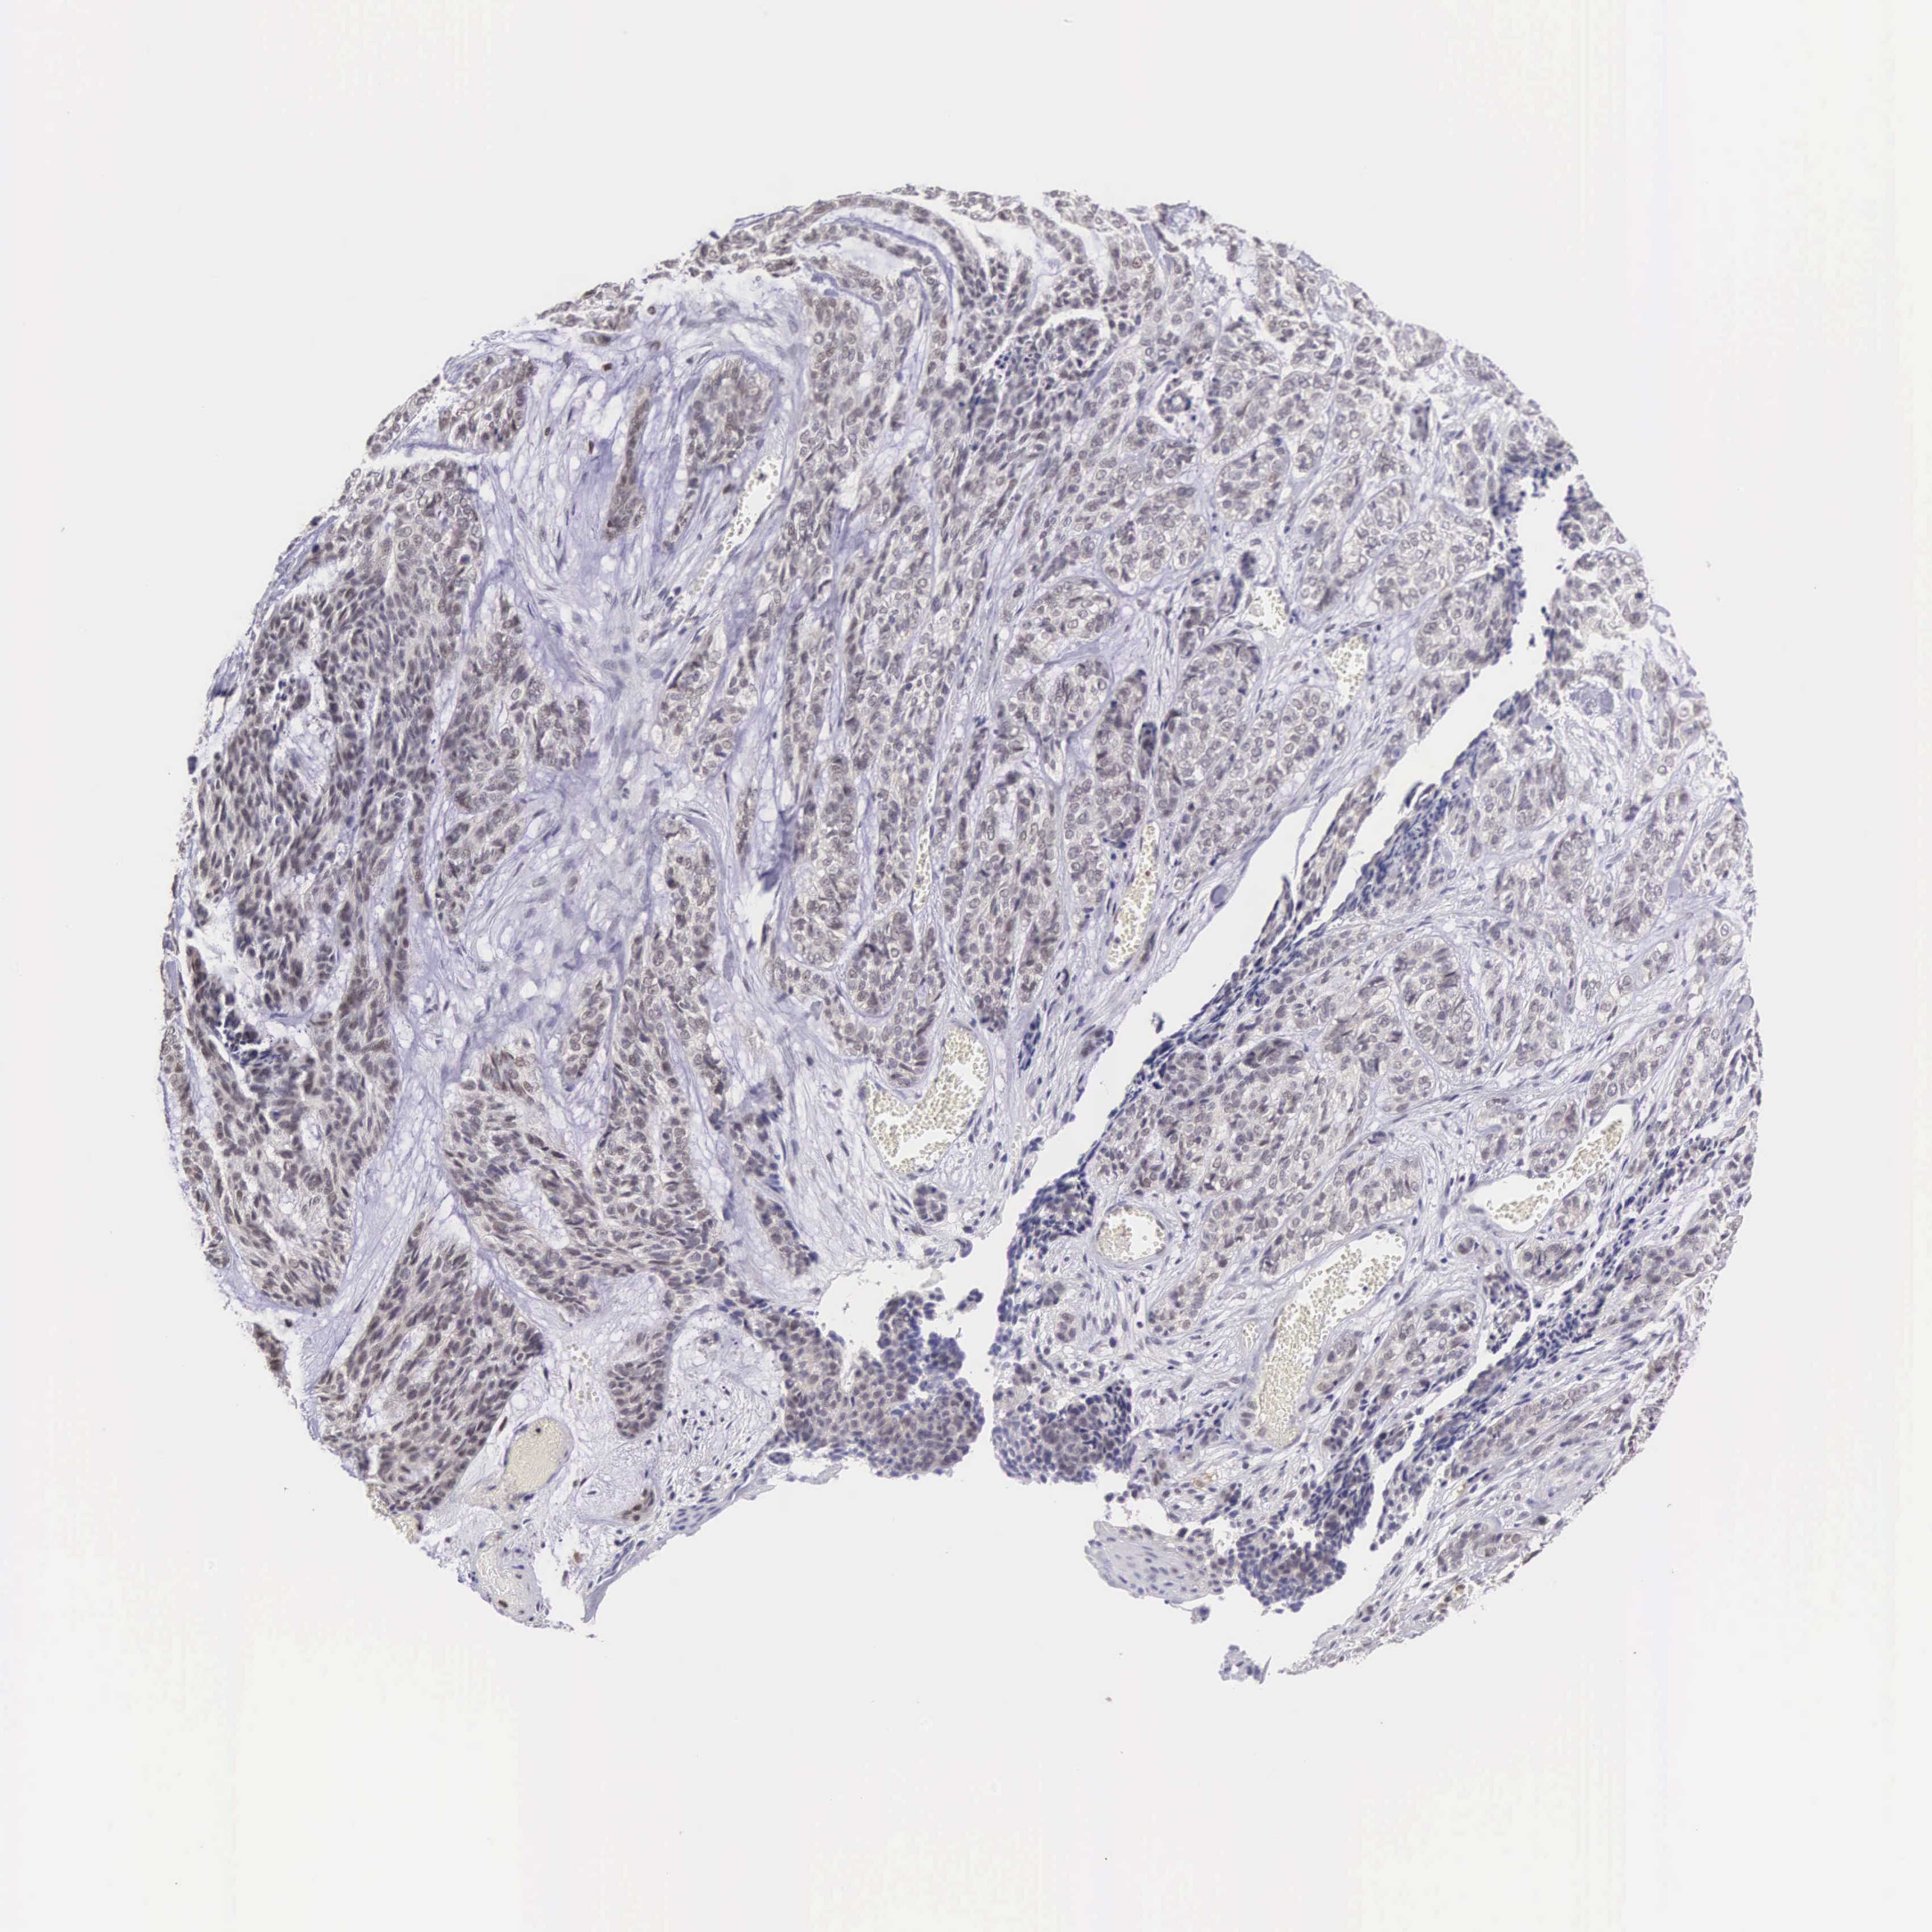

SKIN CANCER - Protein expressioni

A mouse-over function shows sample information and annotation data. Click on an image to view it in a full screen mode. Samples can be filtered based on level of antibody staining by selecting one or several of the following categories: high, medium, low and not detected. The assay and annotation is described here.

Antibody staining in the annotated cell types in the current human tissue is reported as not detected, low, medium, or high, based on conventional immunohistochemistry profiling in selected tissues. This score is based on the combination of the staining intensity and fraction of stained cells.

Each image is clickable and will lead to virtual microscopy that enables deeper exploration of all samples and also displays staining intensity scores, fraction scores and subcellular localization as well as patient and tissue information for each sample.

Antibody HPA000804

Staining

Intensity

Strong

Moderate

Weak

Negative

Quantity

>75%

75%-25%

<25%

None

Location

Nuclear

Cytoplasmic/membranous

Cytoplasmic/membranous,nuclear

Squamous cell carcinoma, NOS

Basal cell carcinoma